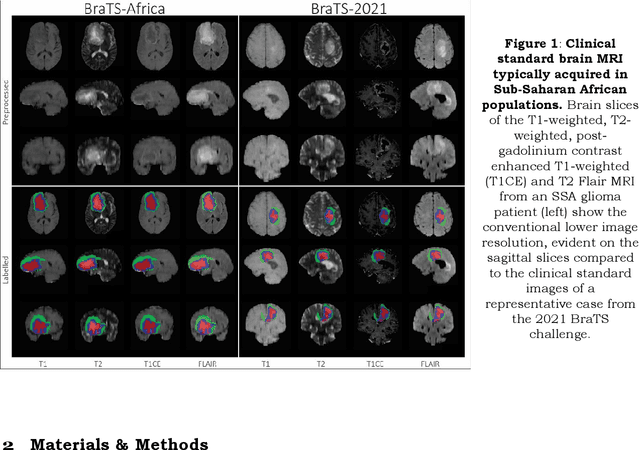

Abstract:Automating brain tumor segmentation using deep learning methods is an ongoing challenge in medical imaging. Multiple lingering issues exist including domain-shift and applications in low-resource settings which brings a unique set of challenges including scarcity of data. As a step towards solving these specific problems, we propose Convolutional adapter-inspired Parameter-efficient Fine-tuning (PEFT) of MedNeXt architecture. To validate our idea, we show our method performs comparable to full fine-tuning with the added benefit of reduced training compute using BraTS-2021 as pre-training dataset and BraTS-Africa as the fine-tuning dataset. BraTS-Africa consists of a small dataset (60 train / 35 validation) from the Sub-Saharan African population with marked shift in the MRI quality compared to BraTS-2021 (1251 train samples). We first show that models trained on BraTS-2021 dataset do not generalize well to BraTS-Africa as shown by 20% reduction in mean dice on BraTS-Africa validation samples. Then, we show that PEFT can leverage both the BraTS-2021 and BraTS-Africa dataset to obtain mean dice of 0.8 compared to 0.72 when trained only on BraTS-Africa. Finally, We show that PEFT (0.80 mean dice) results in comparable performance to full fine-tuning (0.77 mean dice) which may show PEFT to be better on average but the boxplots show that full finetuning results is much lesser variance in performance. Nevertheless, on disaggregation of the dice metrics, we find that the model has tendency to oversegment as shown by high specificity (0.99) compared to relatively low sensitivity(0.75). The source code is available at https://github.com/CAMERA-MRI/SPARK2024/tree/main/PEFT_MedNeXt

Abstract:A critical challenge for tumour segmentation models is the ability to adapt to diverse clinical settings, particularly when applied to poor-quality neuroimaging data. The uncertainty surrounding this adaptation stems from the lack of representative datasets, leaving top-performing models without exposure to common artifacts found in MRI data throughout Sub-Saharan Africa (SSA). We replicated a framework that secured the 2nd position in the 2022 BraTS competition to investigate the impact of dataset composition on model performance and pursued four distinct approaches through training a model with: 1) BraTS-Africa data only (train_SSA, N=60), 2) BraTS-Adult Glioma data only (train_GLI, N=1251), 3) both datasets together (train_ALL, N=1311), and 4) through further training the train_GLI model with BraTS-Africa data (train_ftSSA). Notably, training on a smaller low-quality dataset alone (train_SSA) yielded subpar results, and training on a larger high-quality dataset alone (train_GLI) struggled to delineate oedematous tissue in the low-quality validation set. The most promising approach (train_ftSSA) involved pre-training a model on high-quality neuroimages and then fine-tuning it on the smaller, low-quality dataset. This approach outperformed the others, ranking second in the MICCAI BraTS Africa global challenge external testing phase. These findings underscore the significance of larger sample sizes and broad exposure to data in improving segmentation performance. Furthermore, we demonstrated that there is potential for improving such models by fine-tuning them with a wider range of data locally.

Abstract:Gliomas are the most common type of primary brain tumors. Although gliomas are relatively rare, they are among the deadliest types of cancer, with a survival rate of less than 2 years after diagnosis. Gliomas are challenging to diagnose, hard to treat and inherently resistant to conventional therapy. Years of extensive research to improve diagnosis and treatment of gliomas have decreased mortality rates across the Global North, while chances of survival among individuals in low- and middle-income countries (LMICs) remain unchanged and are significantly worse in Sub-Saharan Africa (SSA) populations. Long-term survival with glioma is associated with the identification of appropriate pathological features on brain MRI and confirmation by histopathology. Since 2012, the Brain Tumor Segmentation (BraTS) Challenge have evaluated state-of-the-art machine learning methods to detect, characterize, and classify gliomas. However, it is unclear if the state-of-the-art methods can be widely implemented in SSA given the extensive use of lower-quality MRI technology, which produces poor image contrast and resolution and more importantly, the propensity for late presentation of disease at advanced stages as well as the unique characteristics of gliomas in SSA (i.e., suspected higher rates of gliomatosis cerebri). Thus, the BraTS-Africa Challenge provides a unique opportunity to include brain MRI glioma cases from SSA in global efforts through the BraTS Challenge to develop and evaluate computer-aided-diagnostic (CAD) methods for the detection and characterization of glioma in resource-limited settings, where the potential for CAD tools to transform healthcare are more likely.